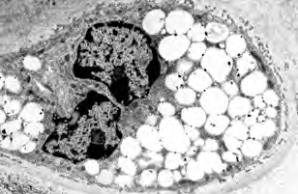

Project 6: Molecular analysis of the bidirectional crosstalk between bone and lipid metabolism